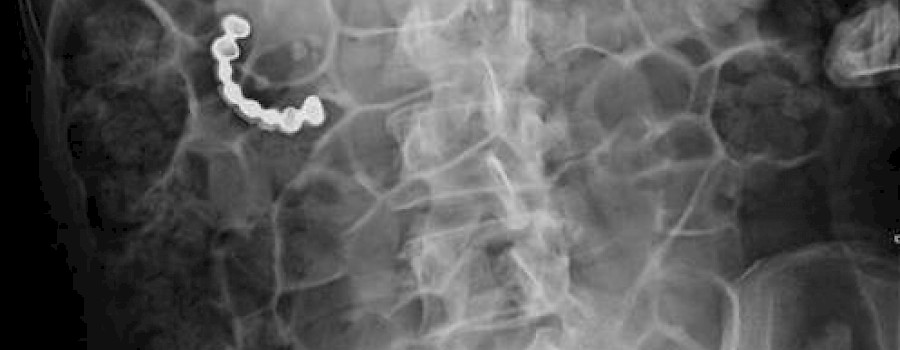

Röntgenzeichen sind in der klinischen Befundung eine wertvolle Hilfe. Die meisten Röntgenzeichen sind so typisch, dass sie gemeinsam mit den klinischen Befunden eine Diagnose beweisen.